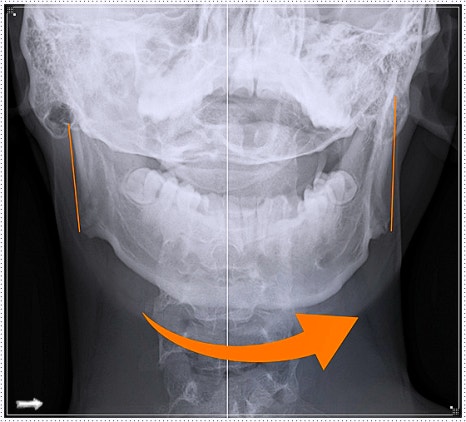

턱이 삐뚤어졌다는 느낌이 드는데 그냥 착각일까요?

거울을 봤을 때 턱이 살짝 한쪽으로 치우쳐 보인다고 느끼는 분들이 있습니다.

대부분은 자세나 습관에서 비롯된 문제입니다.

평소 한쪽으로 기대앉거나 턱을 괴는 습관이 있다면 돌아보셔야 합니다.

이처럼 턱 위치의 이상은 단순히 외형상의 문제를 넘어 머리·목·어깨 통증으로 이어질 수 있습니다.

턱 주변 근육이 긴장되면 두통, 이명, 어지럼증 등의 증상으로 나타나기도 하죠.

따라서 턱에서 소리가 나거나, 턱이 뻐근하고 입을 벌릴 때 걸리는 느낌이 든다면 조기에 전문가의 도움을 받는 것이 좋습니다.